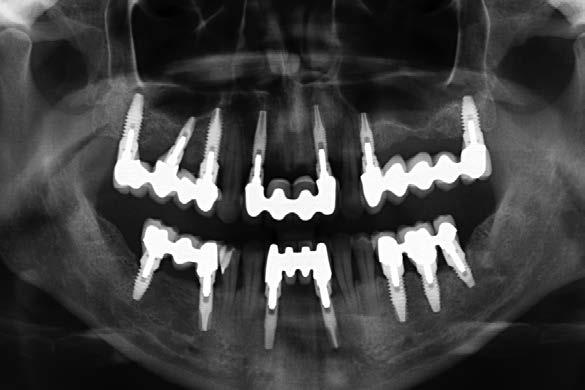

Figura 1. Radiografía panorámica inicial que muestra la enfermedad periodontal avanzada de la paciente, con ausencia de varias piezas dentales y otras de mal pronóstico.

Figura 4. Radiografía tras la primera fasae del tratamiento, con exodoncias realizadas y ferulización de dientes remanentes.

La paciente continúa en seguimiento. A los 8 años, la estabilidad de los tejidos duros y blandos, así como la estética de la rehabilitación, era completa (Figura 9-11). A los 12 años se observó

una buena progresión del tratamiento, sin cambios reseñables (Figura 1214). A los 20 años de seguimiento se constató una evolución estable, sin pérdida ósea en dientes ni implantes, y con buena salud de los tejidos periimplantarios (Figura 15-17).

En este contexto, también se analizó la distribución de implantes por cuadrante: 2, 3 o 4. Tal como se ha demostrado en investigaciones previas de nuestro grupo de estudio, no se

observaron diferencias clínicas significativas entre estas configuraciones en cuanto a pérdida ósea o comportamiento tisular, lo cual se ve claramente reflejado en este caso clínico con seguimiento a largo plazo.19-21

Figura 11. Radiografía a los 8 años de seguimiento, que muestra estabilidad de los tejidos duros con el tratamiento realizado.

Figura 14. Radiografía a los 12 años de seguimiento, con comportamiento estable de dientes e implantes.

Figura 17. Radiografía final que evidencia la estabilidad completa de los tratamientos a los 20 años.